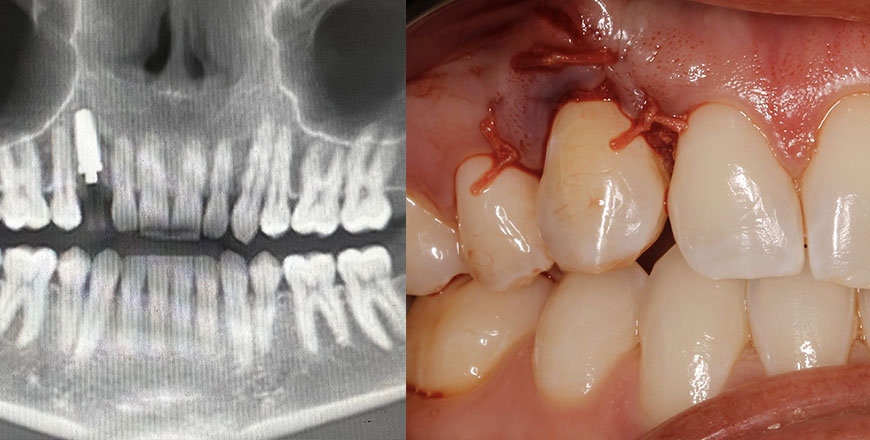

Real Case Applications

Content grounded in actual clinical scenarios and outcomes.

Stay sharp and up to date. Dive deep into real-world cases and techniques guided by expert instructors, and bring back practical skills to your practice.